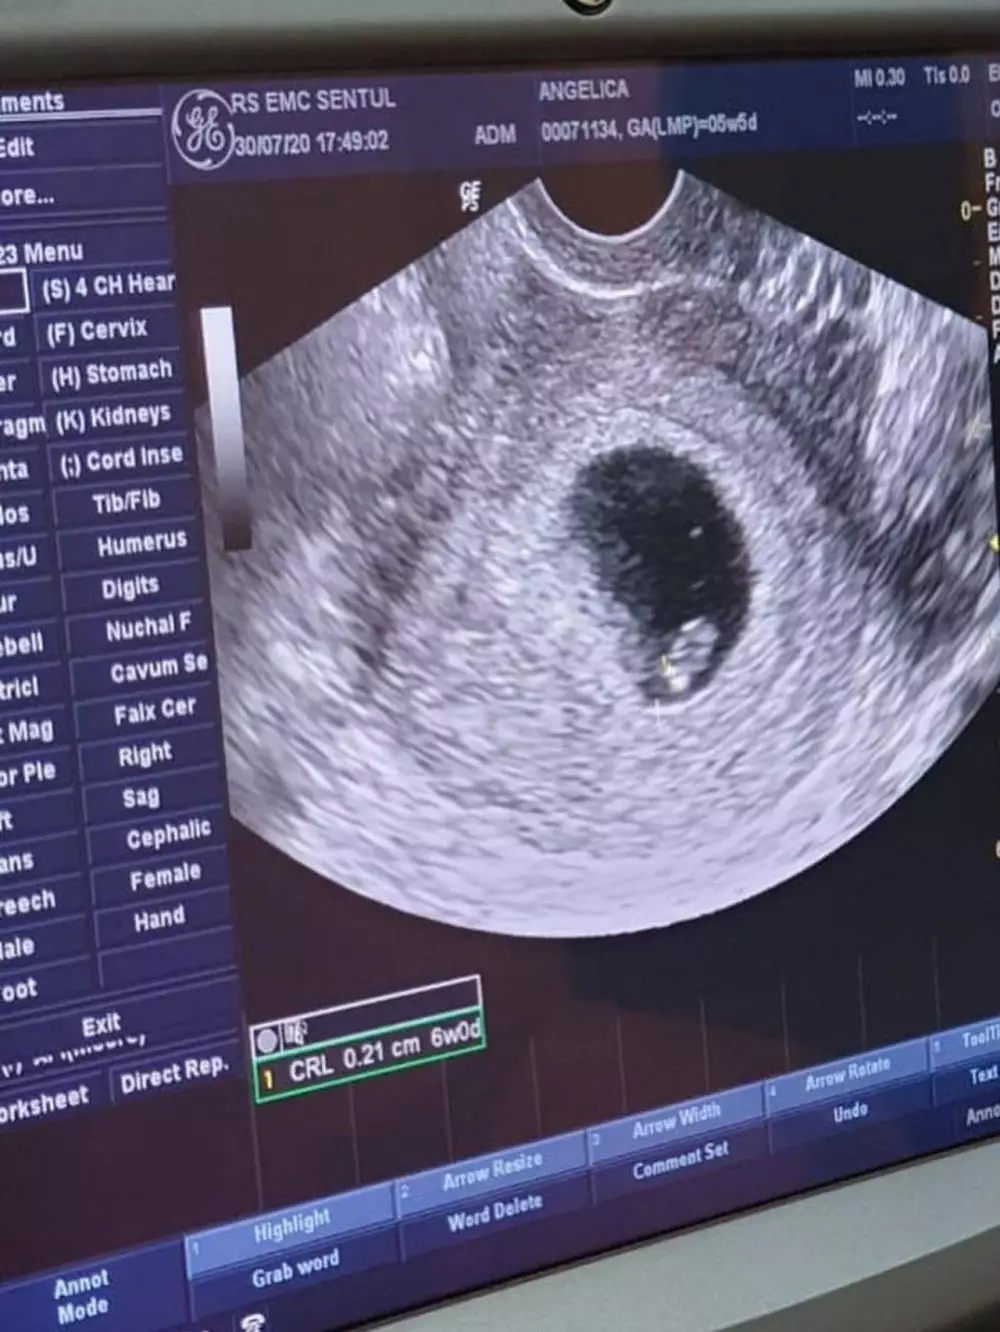

1. Sebulan setelah menikah, Angelica Simperler mengumumkan bahwa dirinya tengah mengandung anak pertama.

foto: Instagram/@angelicasimp.new

3. Seperti wanita hamil pada umumnya, Angelica rajin kontrol kandungan ditemani sang suami. Ini adalah momen Angelica umumkan jenis kelamin sang anak.